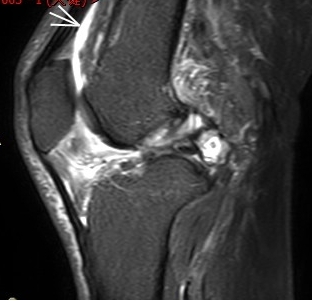

1. “咯吱響”+“卡頓感”——半月板的“碎玻璃警報”

場景:下蹲時膝蓋“咯噔”彈響,起身像被“卡住”

MRI偵查:精準(zhǔn)捕捉半月板撕裂或變性(半月板內(nèi)高信號),避免拖成“關(guān)節(jié)交鎖”

(半月板撕裂)